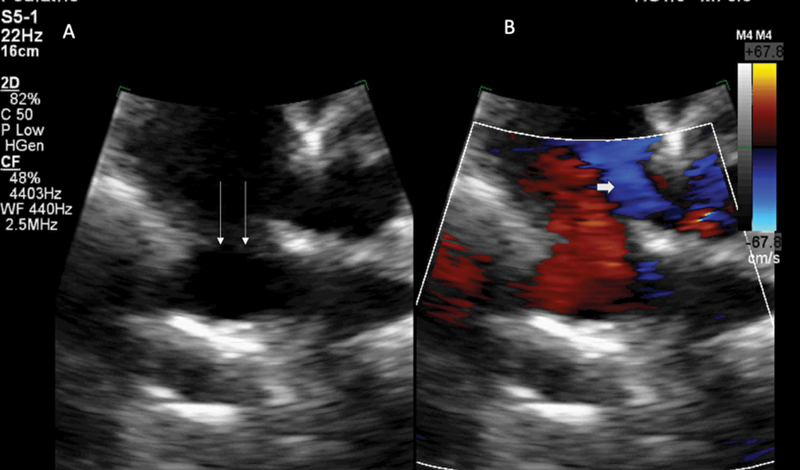

全肺静脉连接异常(TAPVC)是指所有肺静脉均异常排入体循环。心内型通常是所有肺静脉经冠状窦排入右心房。肺静脉直接与右心房相连的情况非常罕见,主要与右心房异位症有关。在此,我们介绍了一例罕见的 10 岁男童 TAPVC 病例,其特点是所有肺静脉均以非常规方式直接排入右心房,冠状动脉窦正常,无右心房异位。耐人寻味的是,计算机断层扫描成像显示出令人难以置信的罕见的肺部、血管和骨骼并存异常。这些畸形包括右肺无肺裂、左侧环状主动脉弓存在牛状分支模式、双侧颈肋骨和 C7 椎体融合异常。据我们所知,在 TAPVC 罕见引流模式的背景下,这种独特的并存异常组合以前从未在科学文献中报道过。

Total anomalous pulmonary venous connection (TAPVC) is anomalous drainage of all pulmonary veins into systemic circulation. The intracardiac type typically entails the drainage of all the pulmonary veins into the right atrium, via the coronary sinus. The connection of the pulmonary veins directly into the right atrium is exceptionally rare and has been primarily reported with right atrial isomerism. Herein, we presented a remarkable case of TAPVC in a 10-year-old male child, distinguished by an unconventional drainage of all the pulmonary veins directly into the right atrium, with normal coronary sinus and absent right atrial isomerism. Intriguingly, computed tomography imaging revealed a combination of incredibly rare coexistent pulmonary, vascular, and skeletal anomalies. These anomalies included absence of pulmonary fissures in the right lung, presence of left circumflex aortic arch with bovine branching pattern, bilateral cervical ribs, and C7 vertebral fusion anomalies. To our knowledge, this unique combination of coexistent anomalies has not been previously reported in scientific literature in the background of rare drainage pattern of TAPVC.